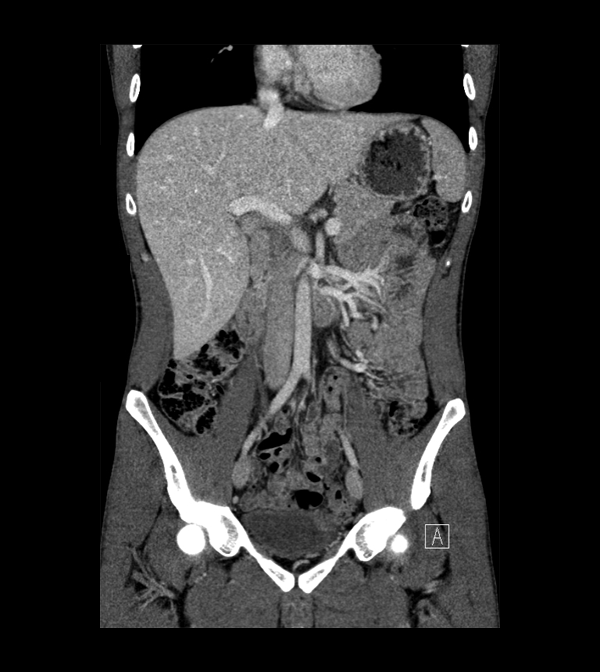

Body

Covers abdominal CT anatomy.